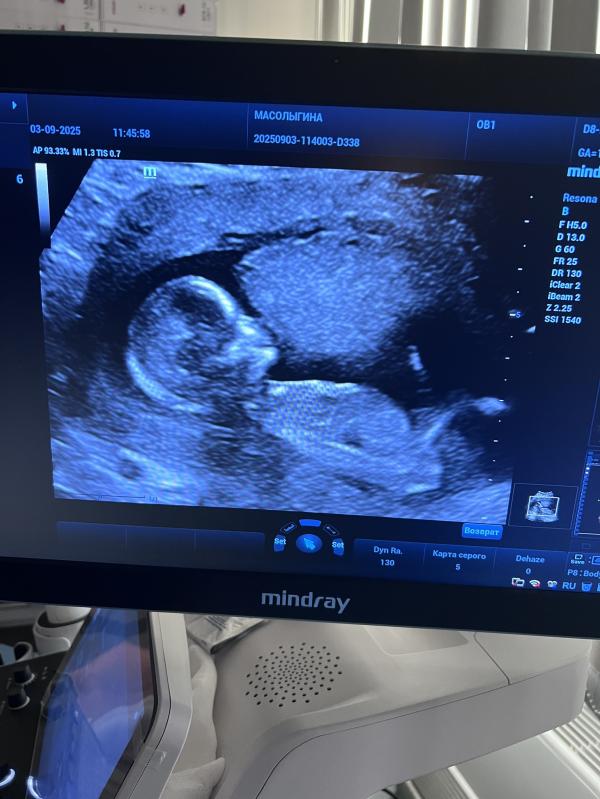

Добрый день,девочки. Кто сталкивался с увеличением ТВП? Норма до 2,5 у меня 2,9. Очень перенервничала вчера на скрининге. А сегодня меня добили в консультации. Теперь не могу успокоиться от истерики🙈тиреотропный гормон 7,3300. Гемоглобин 87. Врач и акушер весь прием общались между собой и только ахали и охали. А я как маленькая сидела и расплакалась. Даже не сообразила какие вопросы задать🙈назначили прием у эндокринолога,сказали ждём анализа крови от генетиков и потом назначат еще один анализ. Кто сталкивался с подобными моментами и что в итоге у Вас было?